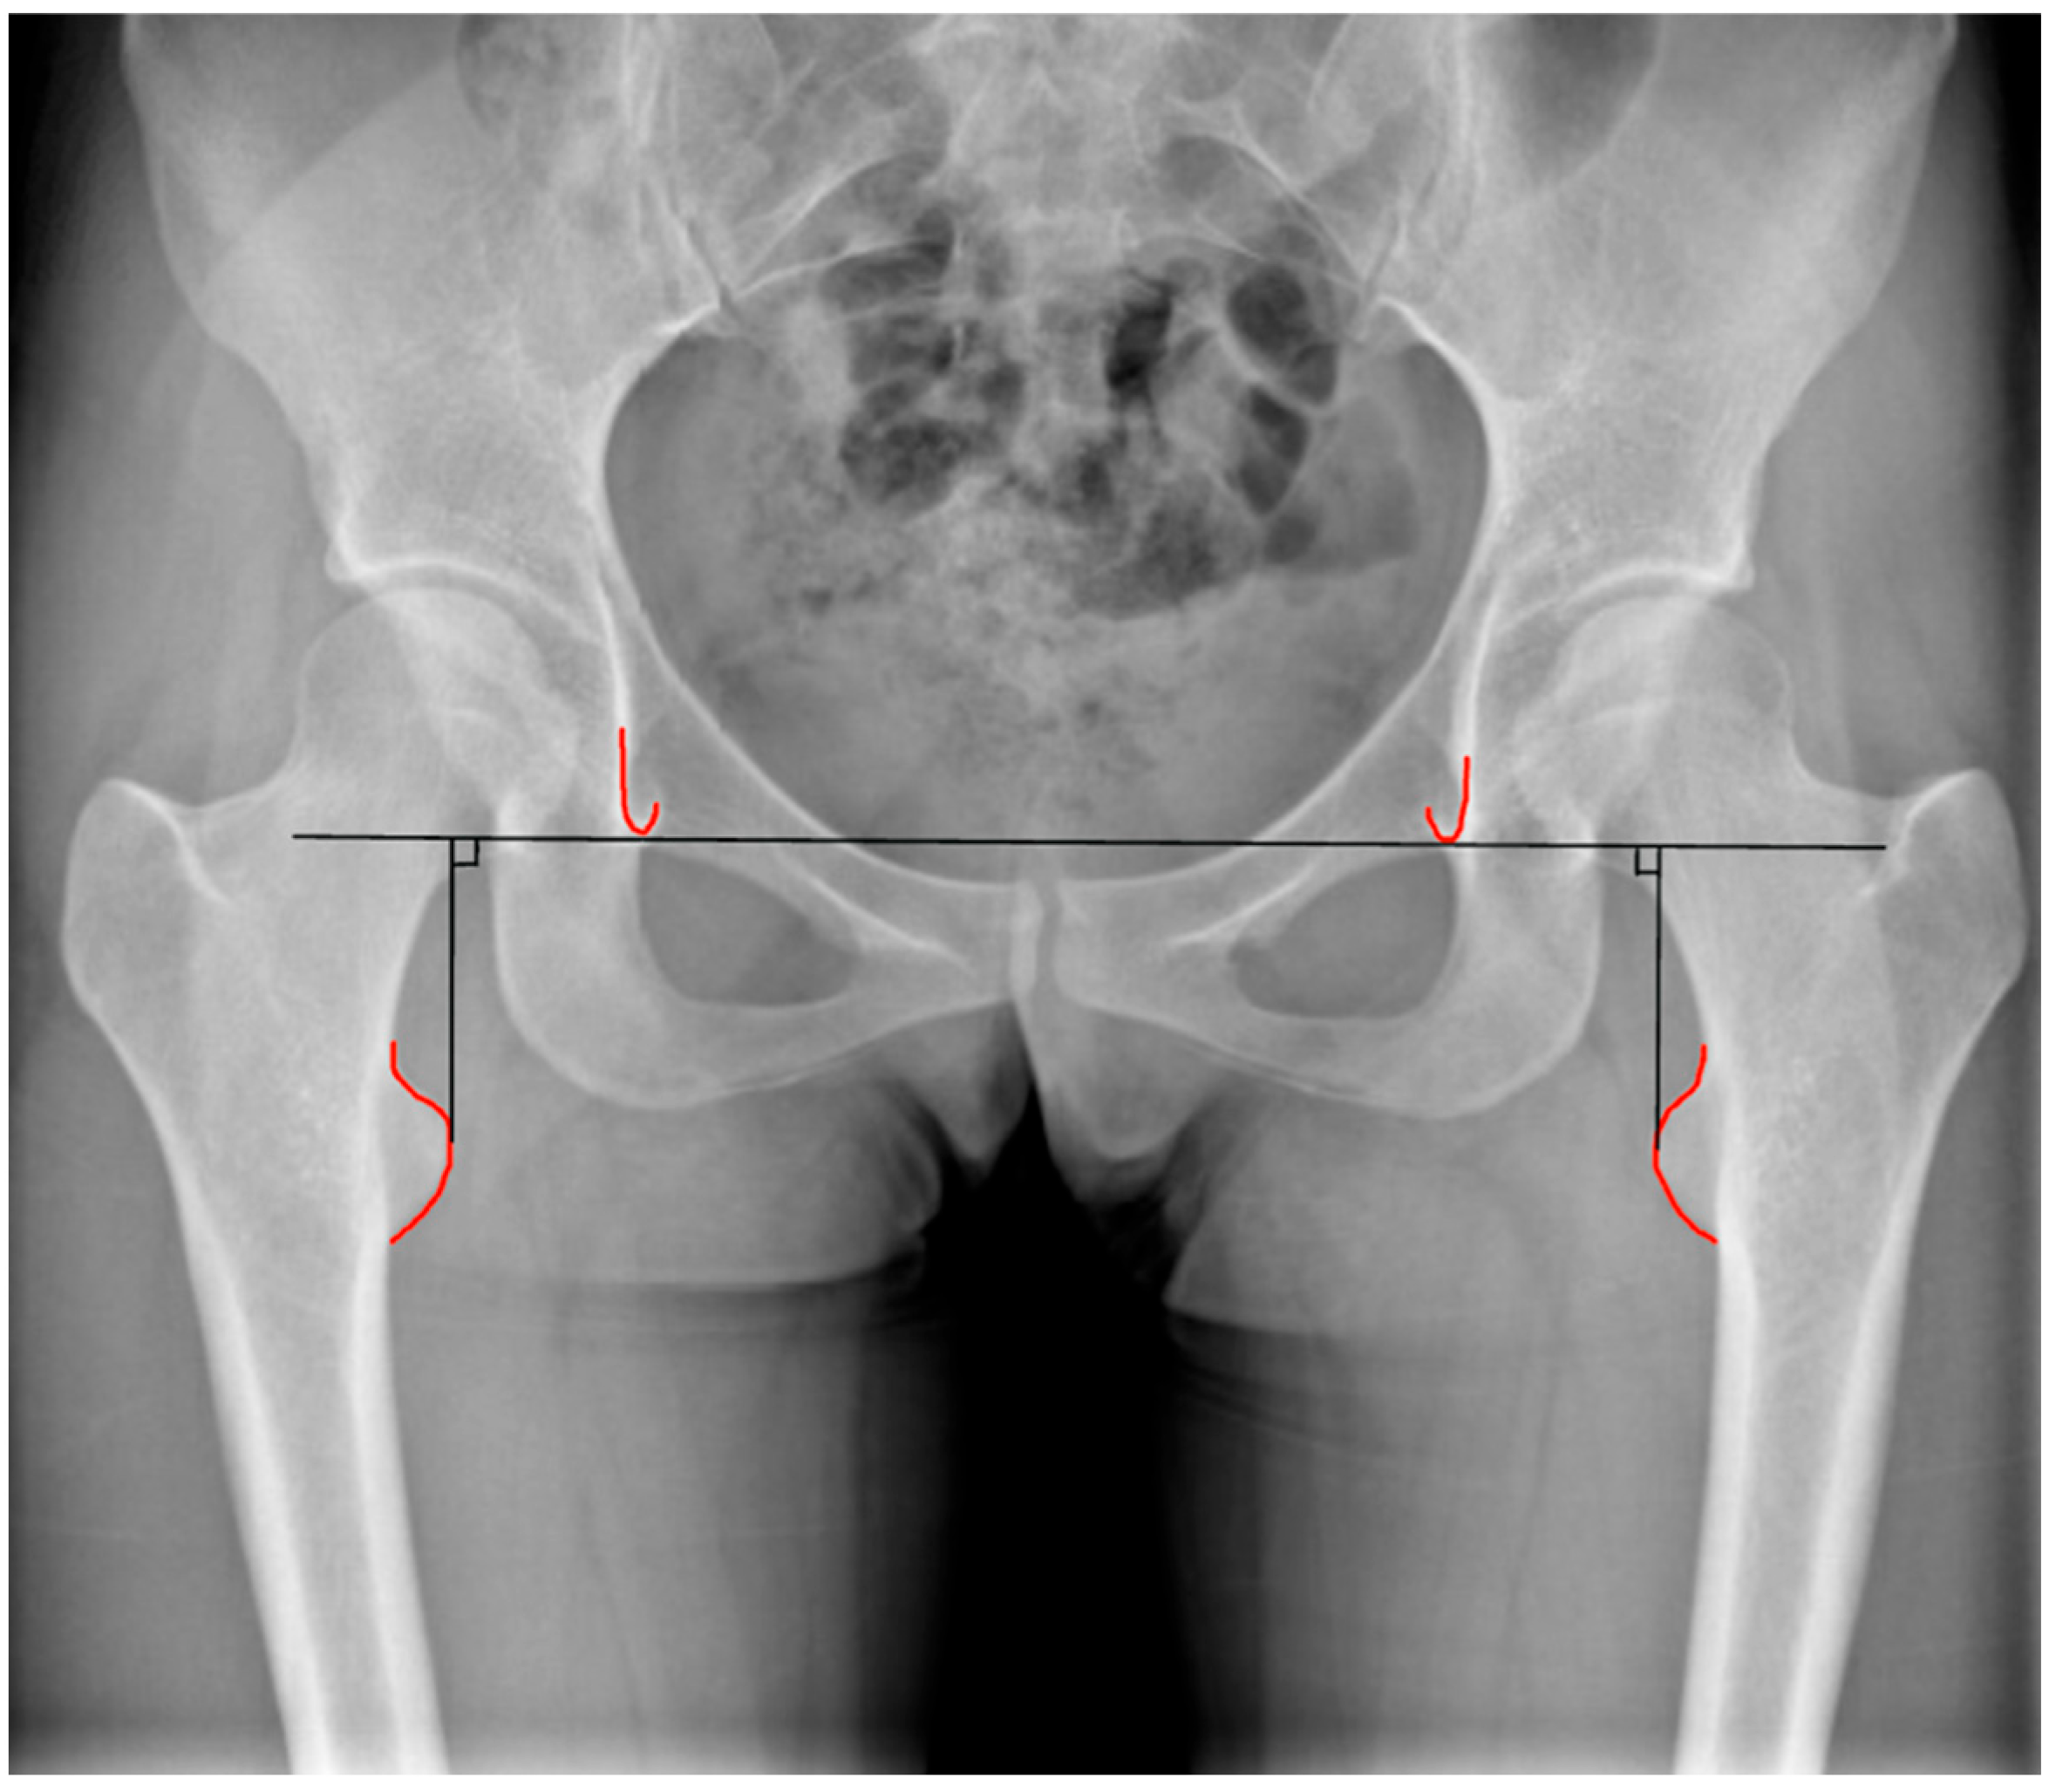

2. Anatomical and Functional Lower Limb Discrepancy: Definition and Assessment

3. Lower Limb Discrepancy in THA

4. Preoperative Planning and Intraoperative Assessment